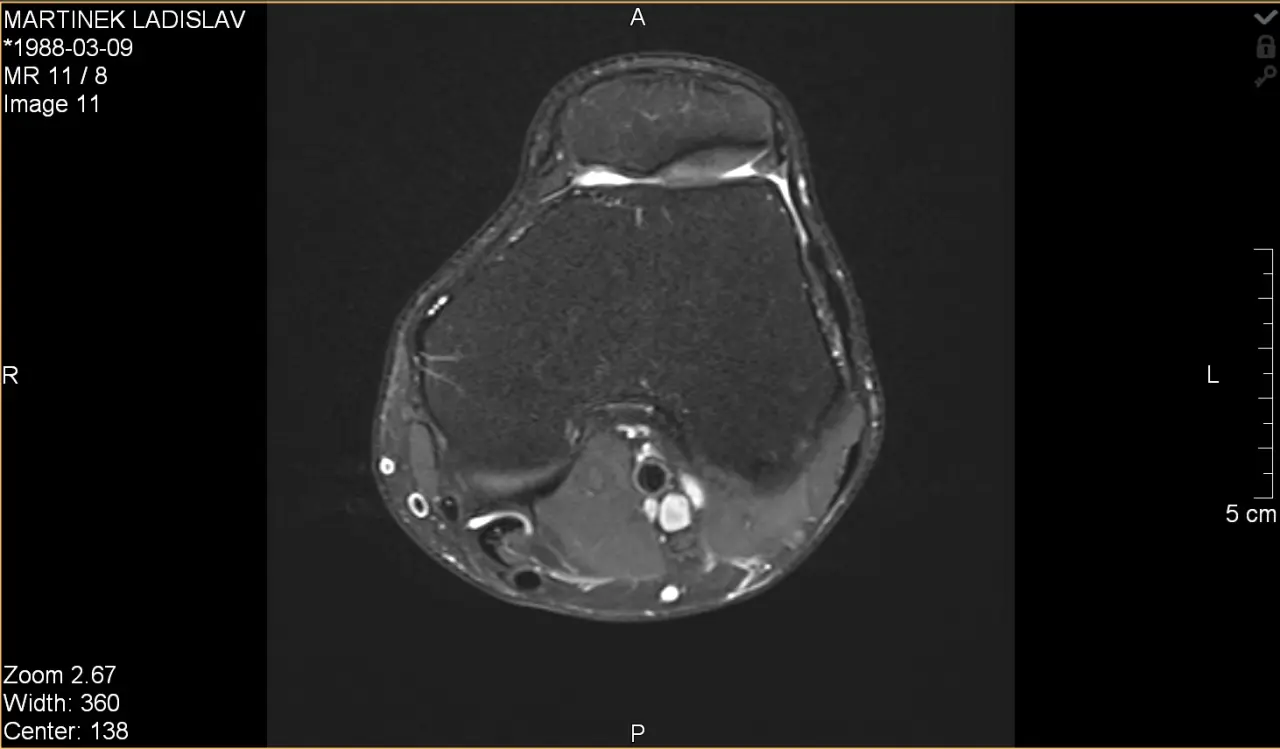

Ladislav Martínek

Cesta bolesti a hledání pomoci

Pomozte Láďovi změnit tento příběh